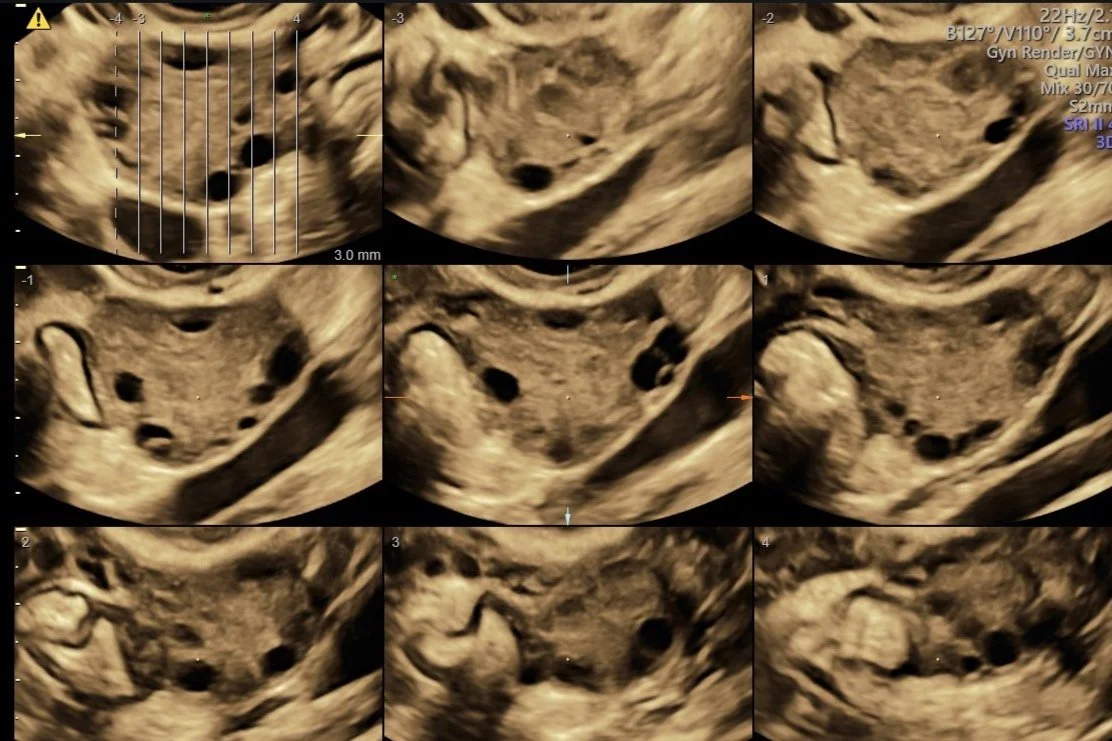

At Trinity Imaging we only offer Gold standard protocols for the assessment of pelvic pathology and pregnancy assessments. Our Gold standard/protocol is to offer every female patient a Transvaginal assessment for gynaecological, early pregnancy, nuchal translucency, Morphology and Growth Scans. This is because the transducer is positioned close to the pelvic organs/pregnancy, producing superior image quality, allowing more accurate and detailed diagnosis.

To acquire the best diagnostic images possible, the examination is routinely performed Transabdominally, followed by a Transvaginal ultrasound (always with your written consent first).